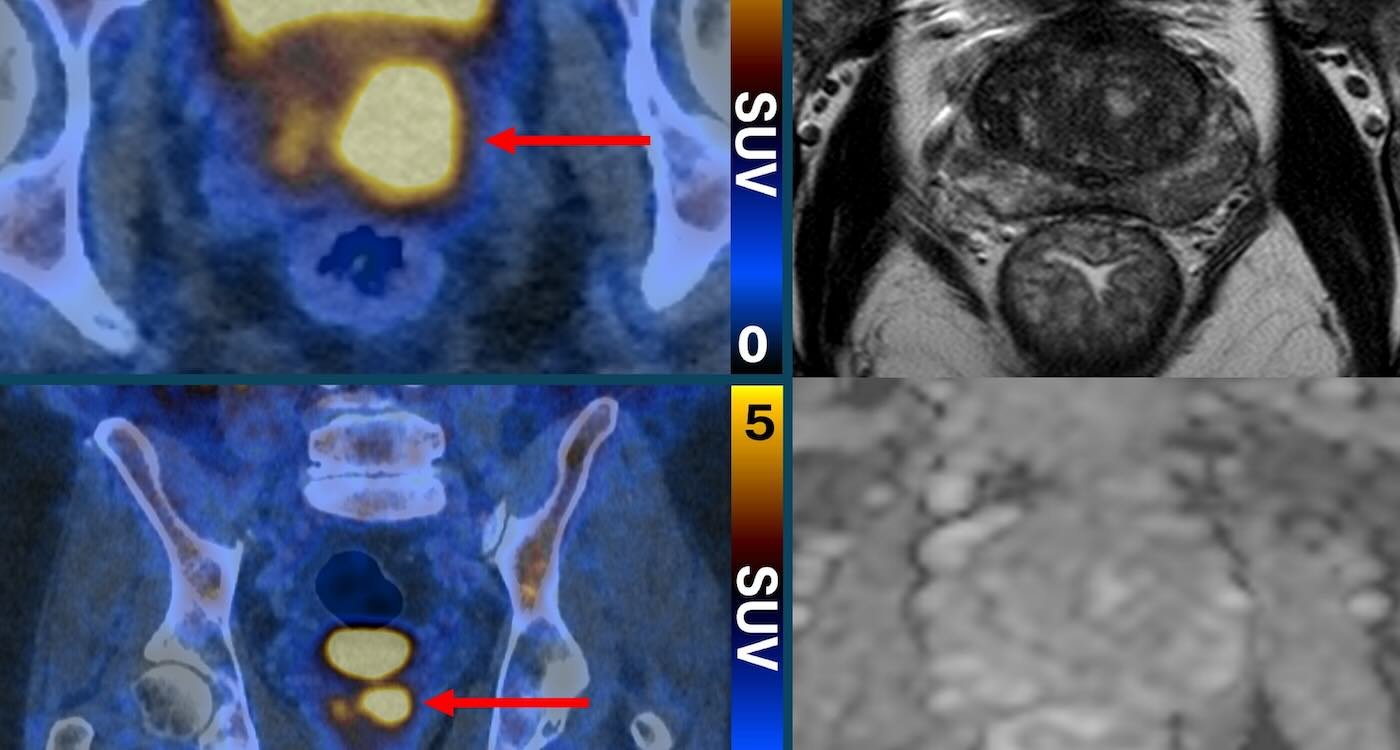

Glowing prostate cancer cells PSMA PET/CT Scan – SWNS

Primary2 found that PSMA PET/CT scanning could identify people who either did not have cancer, or whose cancer was so low-risk or slow-growing it would likely never cause harm.

Those patients did not need a biopsy, while patients with a ‘positive result’ for cancer according to the PSMA PET/CT scan had a biopsy.

Researchers say the approach halved the number of patients who needed a biopsy, without missing any harmful cancers.

For patients who still needed a biopsy, their scan results ensured the procedure was targeted to the suspicious areas identified in the test to minimize complications and improve accuracy.